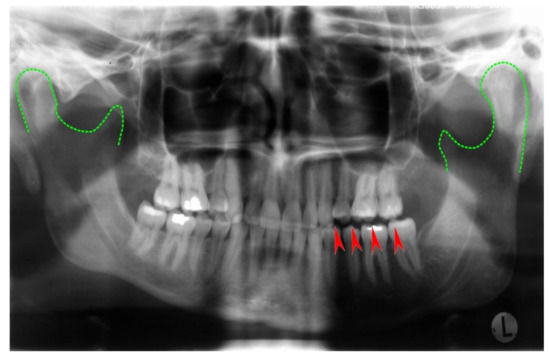

Unilateral mandibular condylar hyperplasia is a rare disease, where one condyle exhibits excessive growth [124,125,126]. A benign tumor of the long bones, osteochondroma, may also affect the mandibular condyle with similar consequences: Condylar growth leads to dislocation of the mandibular body in vertical and/or anterior direction. Asymmetry and occlusal imbalances are frequent consequences (Figure 10 and Figure 11). Treatment includes surgical remodeling or removal of the affected condyle and, if necessary, insertion of a neocondyle.

Figure 10.

Panoramic radiograph of a unilateral condylar hyperplasia on a 38-year-old female patient’s left side. Green dotted lines outline the condyles; arrows indicate non-occlusion in the left bicuspid and molar region. In this case, the panoramic radiograph gives an impression of asymmetry. However, CT and cone beam CT are superior in accuracy.

Figure 11.

Intraoral view of the same patient. Unilateral open bite on the left side and moderate mandibular midline shift are clearly visible. At present, occlusal stability is maintained by an intraoral splint until a definite correction with crowns and overlays in the left mandible will be performed.